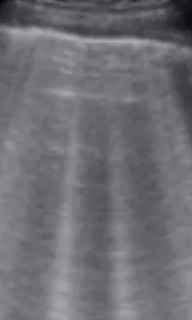

Lactante de 2 años sin antecedentes médicos o quirúrgicos conocidos, con esquema de vacunación completa, refieren los padres 3 días de presentar fiebre de hasta 39 ºC, continua y tos. Al Examen físico con buen estado general, llanto fácil pero consolable, activo y reactivo. Tórax: no tirajes costales, a la auscultación pulmonar con subcrepitante en base pulmonar izquierda e hipoventalación en zona lateroexterna basal izquierda. Se solicita radiografía de tórax en la que hay dudas sobre posible infiltrado basal por lo que se realiza ecografía pulmonar en la que se evidencian líneas B y pequeño derrame pleural.

La ecografía pulmonar es una herramienta valiosa para el diagnóstico de neumonía en niños, mostrando características específicas como consolidación, broncograma aéreo, líneas B y posibles derrames pleurales. Estos hallazgos nos ayudan a diferenciar entre diferentes tipos de neumonía, a evaluar la gravedad del estado del paciente y a resolver dudas radiológicas, sin embargo, lo ideal sería que al ser una prueba no invasiva y más cómoda para el paciente, esta se realizara en el Centro de Salud, evitando radiación innecesaria al paciente.